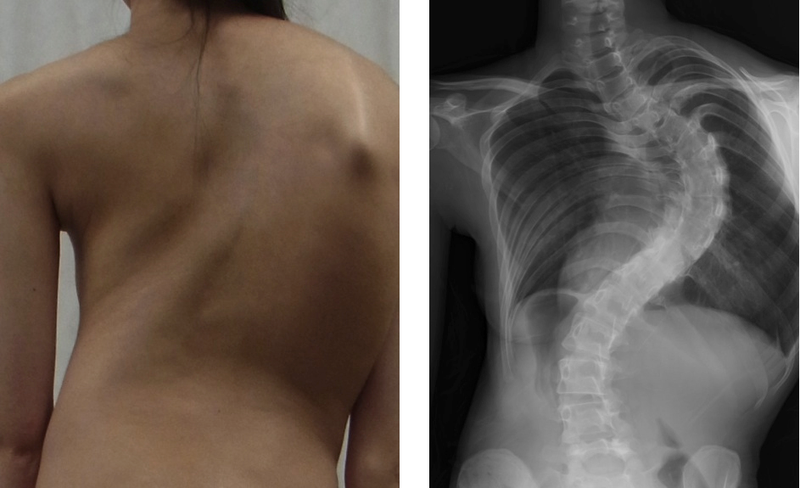

Đôi khi chứng vẹo cột sống rất dễ nhận thấy. Đường cong ở cột sống có thể khiến cơ thể nghiêng sang trái hoặc phải. Nếu bạn bị vẹo cột sống, bạn có thể trông như đang nghiêng sang một bên. Một số người có một bên vai cao hơn bên kia hoặc một bên bả vai nhô ra nhiều hơn bên kia. Nếu cột sống của bạn bị xoắn, một bên lồng ngực có thể nhô ra nhiều hơn khi cúi người xuống. Thông thường, chứng vẹo cột sống không rõ ràng.

Vẹo cột sống vô căn ở thanh thiếu niên là tình trạng cột sống bị cong bất thường, xuất hiện ở tuổi thơ ấu hoặc thanh thiếu niên. Thay vì phát triển thẳng, cột sống phát triển cong sang hai bên, thường có hình chữ “S” hoặc “C” thon dài; xương cột sống cũng hơi xoắn hoặc xoay. Vẹo cột sống ở thanh thiếu niên xuất hiện trong giai đoạn tăng trưởng nhanh chóng của thanh thiếu niên. Trong nhiều trường hợp, đường cong cột sống bất thường vẫn ổn định, mặc dù ở một số trẻ tình trạng này trở nên nghiêm trọng hơn theo thời gian. Không rõ lý do, những đường cong trầm trọng và tiến triển xảy ra thường xuyên hơn ở bé gái so với bé trai. Tuy nhiên, vẹo cột sống nhẹ cũng phổ biến như nhau ở bé gái và bé trai.